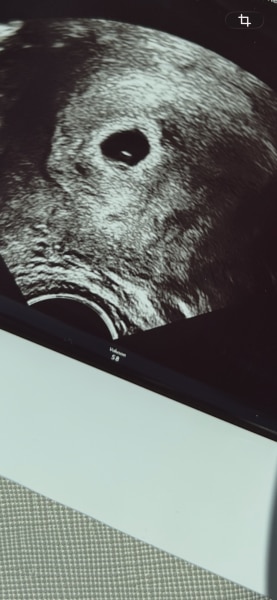

Heute war ich 5+2 bei meinem ersten Frauenarzttermin.  zu sehen war eine kleine fruchthöhle und ein kleiner Dottersack.  Den nächsten Termin habe ich in etwas mehr als 3 Wochen und das ist echt so lang bis man die Gewissheit hat, ob das Herzchen angefangen hat zu schlagen. 🙃 wie ist es bei euch ?  🧡